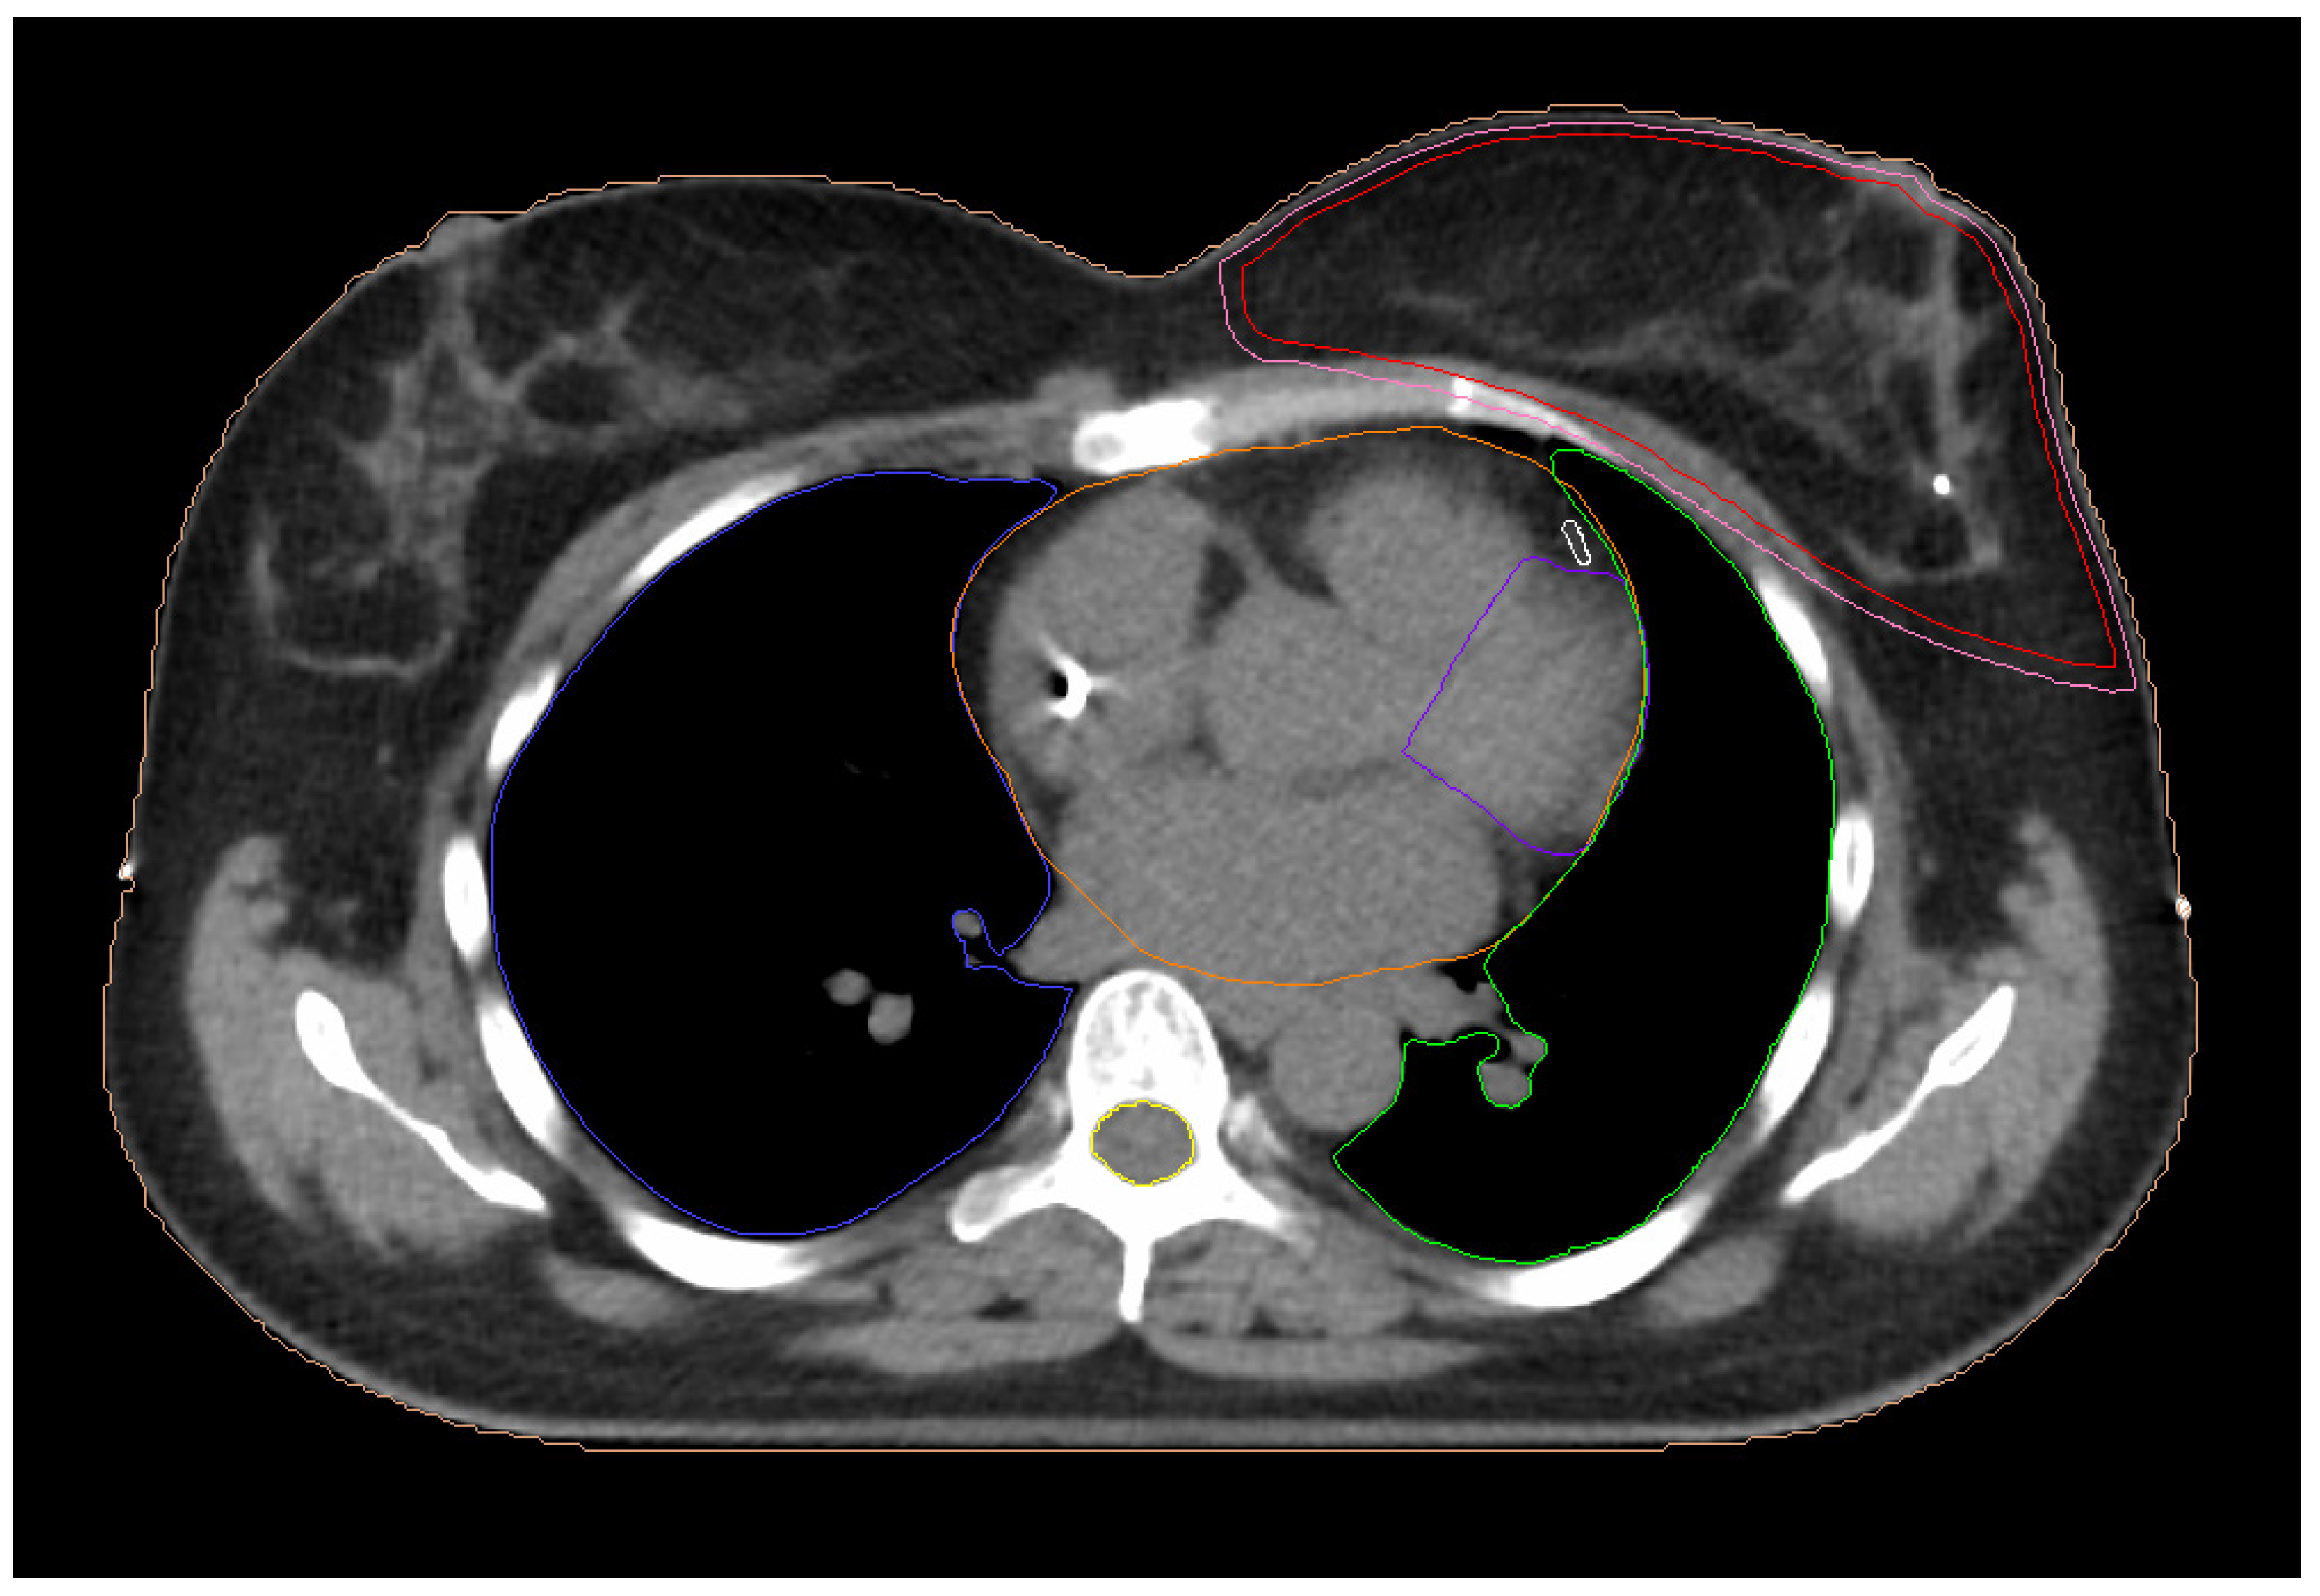

2.3.1. 3D-CRT Technique

2.3.2. Two-Field IMRT Technique (2F-IMRT)

2.3.3. Seven-Field IMRT Technique (7F-IMRT)

2.3.4. Two Partial-Arc VMAT Technique (VMAT1)

2.3.5. Four Partial-Arc VMAT Technique (VMAT2)